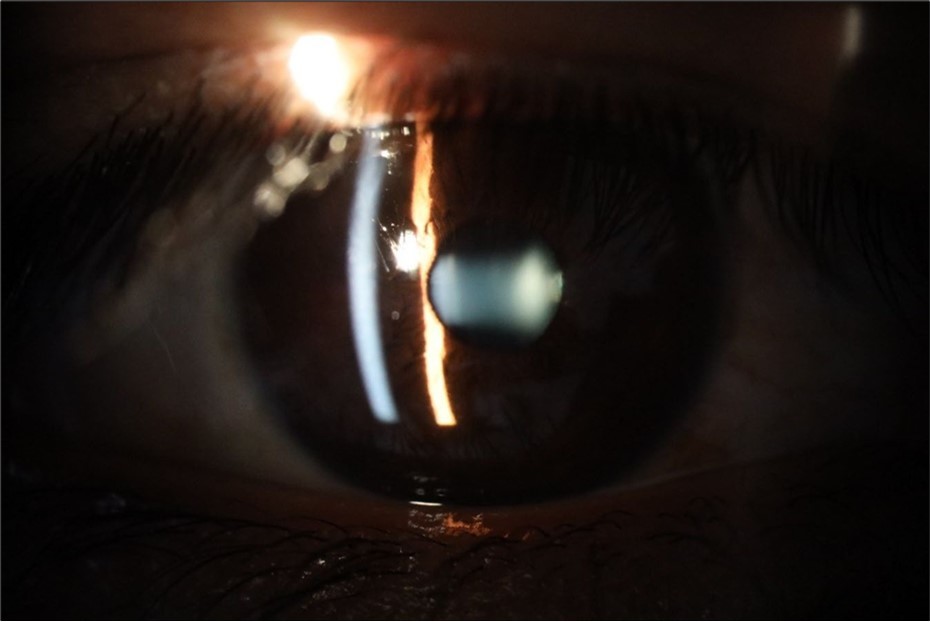

Figure 6.Slit-lamp examination showed a solution of continuity in the left temporal region, which fortunately only affected the conjunctiva and Tenon's capsule, while the sclera was unscathed.

Figure 16.The anterior segment of the right eye shows the vitreous with greater transparency. The cornea and lens, as well as the anterior chamber, are in good condition.